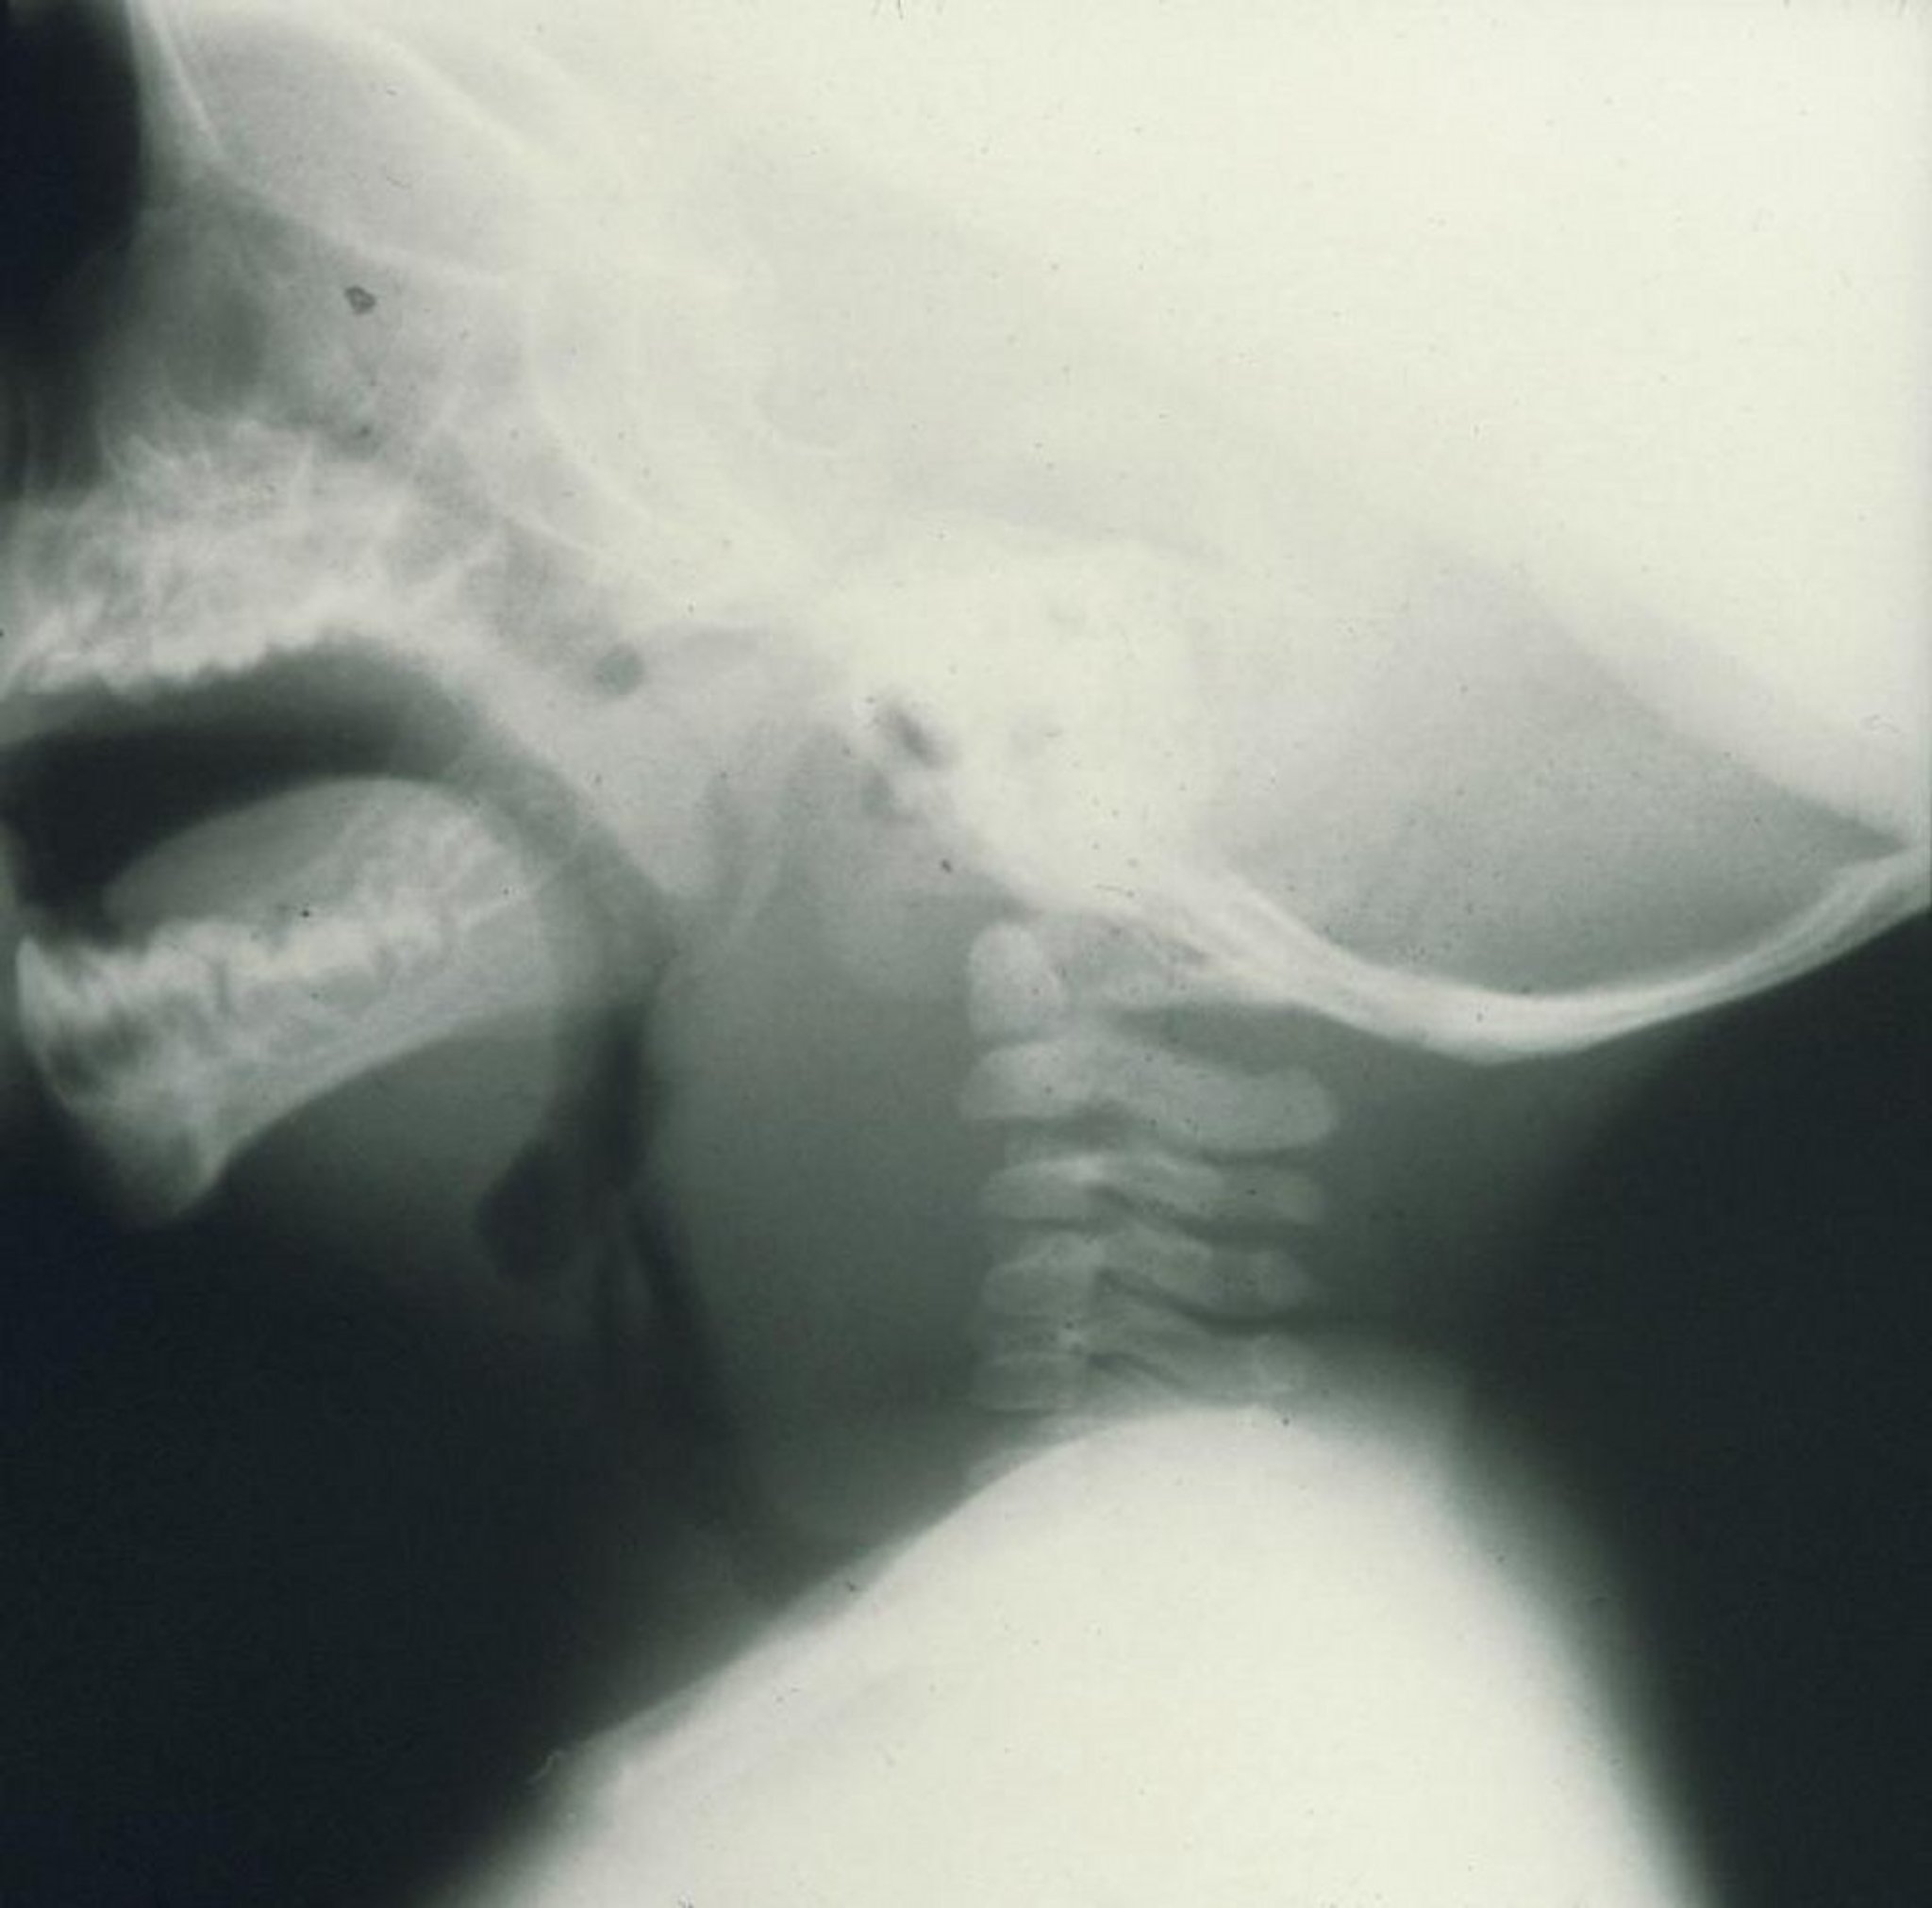

Retropharyngeal Abscess

This lateral x-ray of a child shows marked swelling anterior to the cervical vertebrae caused by a retropharyngeal abscess.

Image provided by Clarence T. Sasaki, MD.